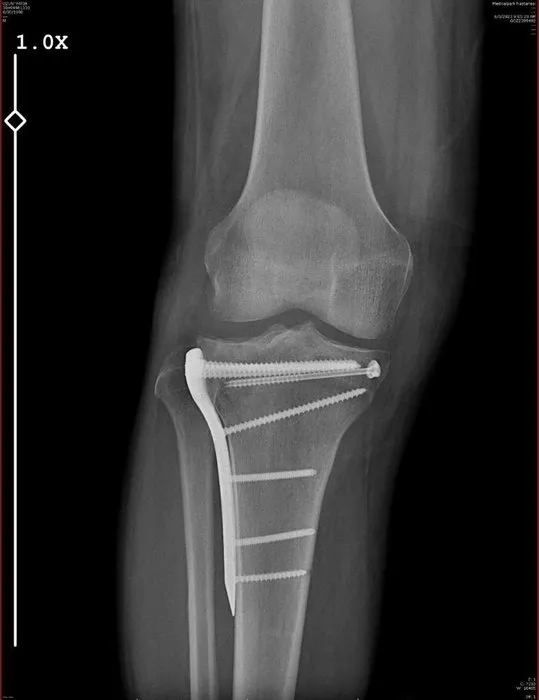

Seyir halindeyken Uzun'un aracının önüne geçip fren yapan polis memuru, daha sonra Uzun'un aracını durdurdu. Fatih Uzun'un yanına gelen polis avukata saldırdı. Aldığı darbeler sonucu bacağı iki yerden kırılan avukat geçirdiği ameliyatlar sonucunda 10 gün hastanede tedavi gördü.